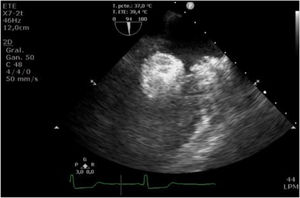

Tras el procedimiento, el paciente fue trasladado al hospital de día donde, a las 2h, inició un episodio de disnea acompañado de náuseas, desaturación e hipotensión. Se detectó una insuficiencia mitral (IM) severa de novo por desplazamiento del dispositivo implantado (figs. 1 y 2). El paciente entró en situación de shock cardiogénico y se trasladó a quirófano de forma emergente.